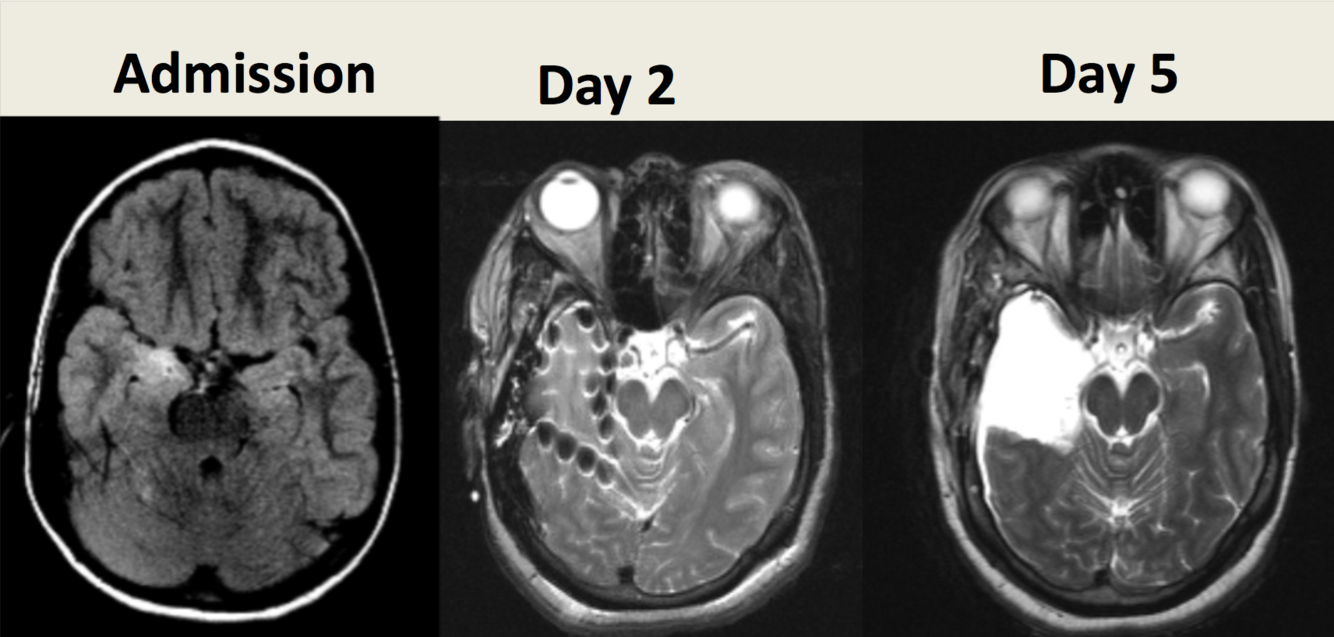

9 y/o M with seizures- 3 MRIs in one week.

Admission: ganglioglioma

Day 2: Intracranial electrodes

Day 5: Temporal lobectomy